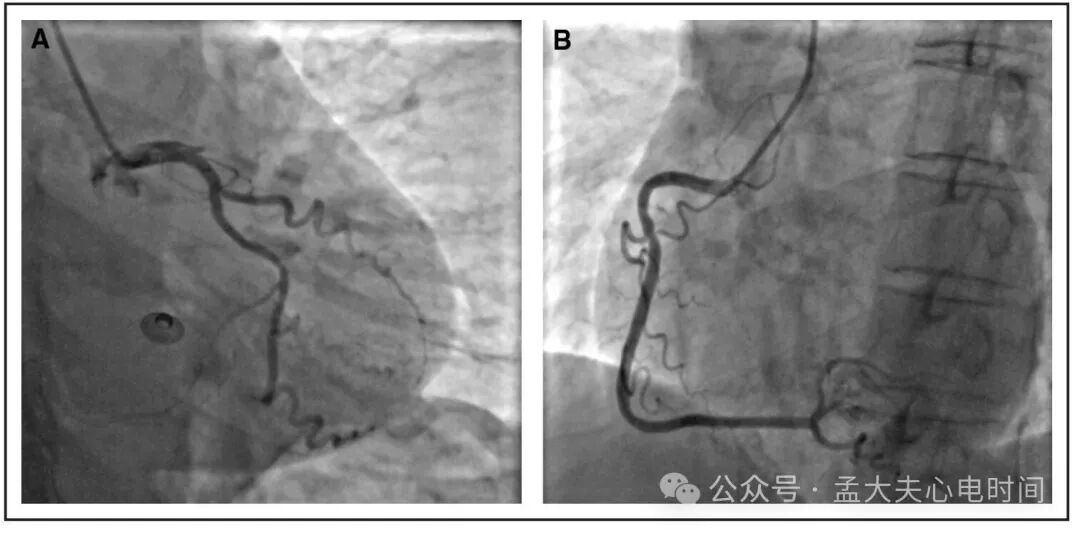

图2: 患者冠脉造影结果。

A:左前降支和左回旋支的冠状动脉造影显示,左主开口处存在 70% 的狭窄,左前降支近端完全性闭塞(100%),左回旋支远端段70%狭窄。

B:右冠状动脉的冠状动脉造影显示右冠状动脉近端段 40% 狭窄。